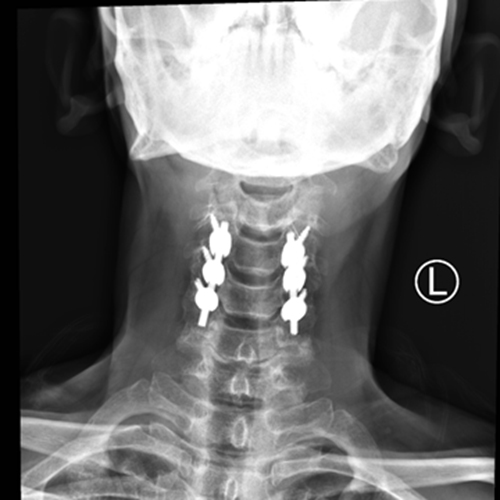

入科后,骨科主任张朝跃教授所带领团队对曾大叔进行查体,发现颈部活动受限,双上肢无法活动,双下肢无法抬离床面,仅有些许肌肉收缩,整个人呈瘫痪状态。为最大化降低创伤对患者神经功能造成的不可逆伤害,尽快恢复神经功能创造条件,经过脊柱外科组上团队讨论后,于7月3日急诊为患者在全麻下行颈椎后路椎板切除+椎管减压+钉棒系统内固定术,手术顺利。

术后复查X片